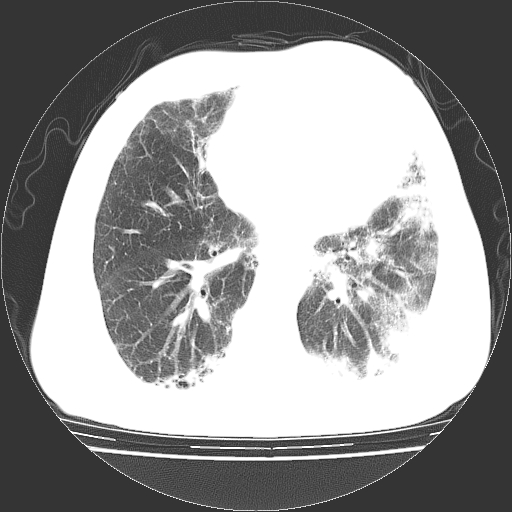

标题: CT25149:男,69岁,反复咳嗽、咳痰五年余,呼吸困难三天。 [打印本页]

男,69岁,反复咳嗽、咳痰五年余,呼吸困难三天。

慢支伴感染、肺气肿、肺心病

慢支伴感染、肺气肿、肺心病!支持!另:间质纤维化!

两肺间质性炎症并感染,左上叶肉芽肿

考虑慢性间质性肺炎并肺间质纤维化。

慢支伴感染、肺气肿、肺心病。双肺间质性改变(间质纤维化)。